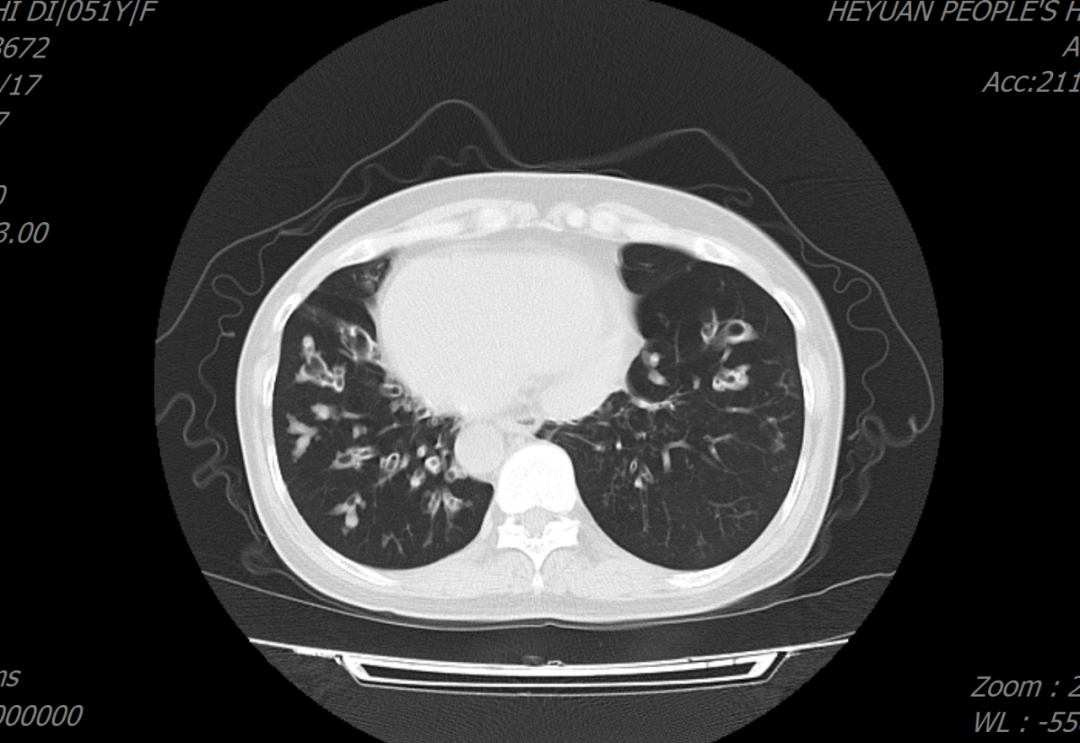

患者周某某,女,51岁,因“反复咳嗽、咳痰30余年,加重5天”入住我院呼吸与危重症医学科,胸部CT示双肺支气管扩张、右位心;入院诊断:支气管扩张症并感染。罗少华主任医师查房分析患者病情指出,患者双肺支气管扩张,右位心伴全内脏转位,需考虑罕见病——“卡塔格内综合征”,结合后续的完善鼻窦CT:双侧筛窦、上颌窦、蝶窦、右侧额窦炎,符合“卡塔格内综合征”的诊断标准。经规范治疗,患者病情好转,予做好健康宣教后出院。

患者胸部CT表现为双肺支气管扩张